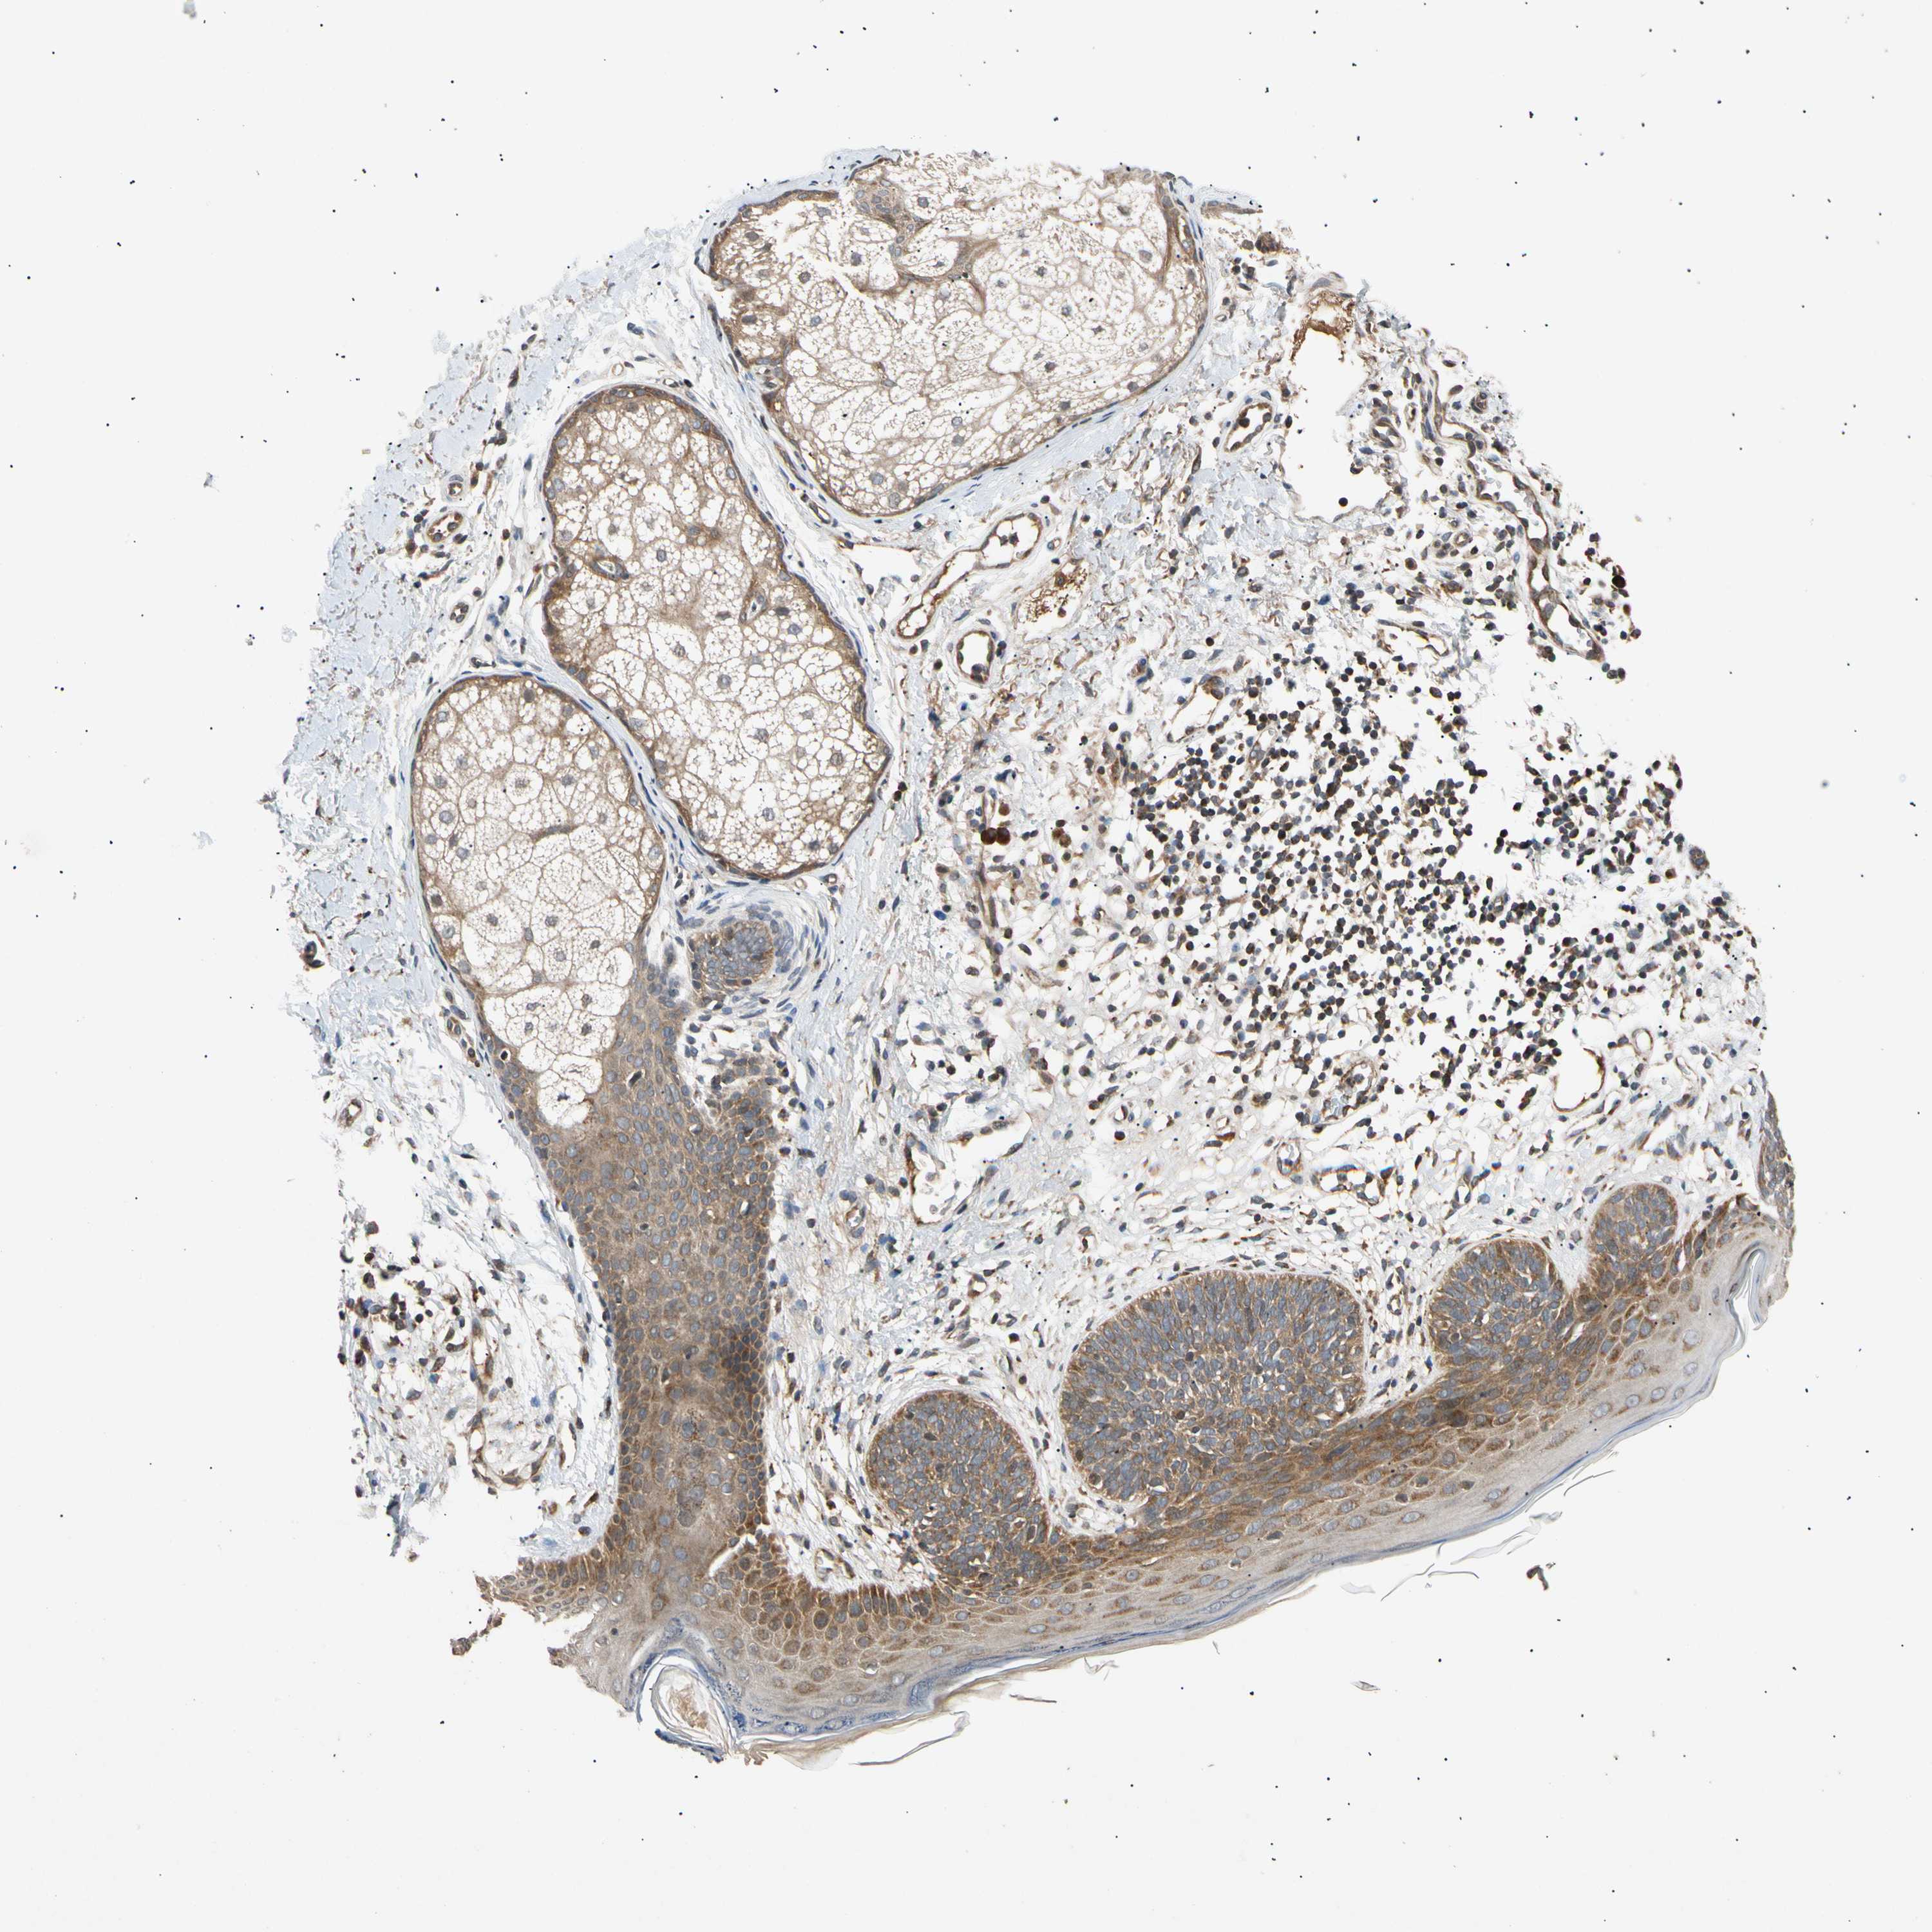

CANCER SKIN CANCER Show tissue menu

Basal cell and squamous cell cancer

SKIN CANCER - Protein expressioni

A mouse-over function shows sample information and annotation data. Click on an image to view it in a full screen mode. Samples can be filtered based on level of antibody staining by selecting one or several of the following categories: high, medium, low and not detected. The assay and annotation is described here.

Each image is clickable and will lead to virtual microscopy that enables deeper exploration of all samples and also displays staining intensity scores, fraction scores and subcellular localization as well as patient and tissue information for each sample.

Antibody HPA006083

Squamous cell carcinoma, NOS

Basal cell carcinoma